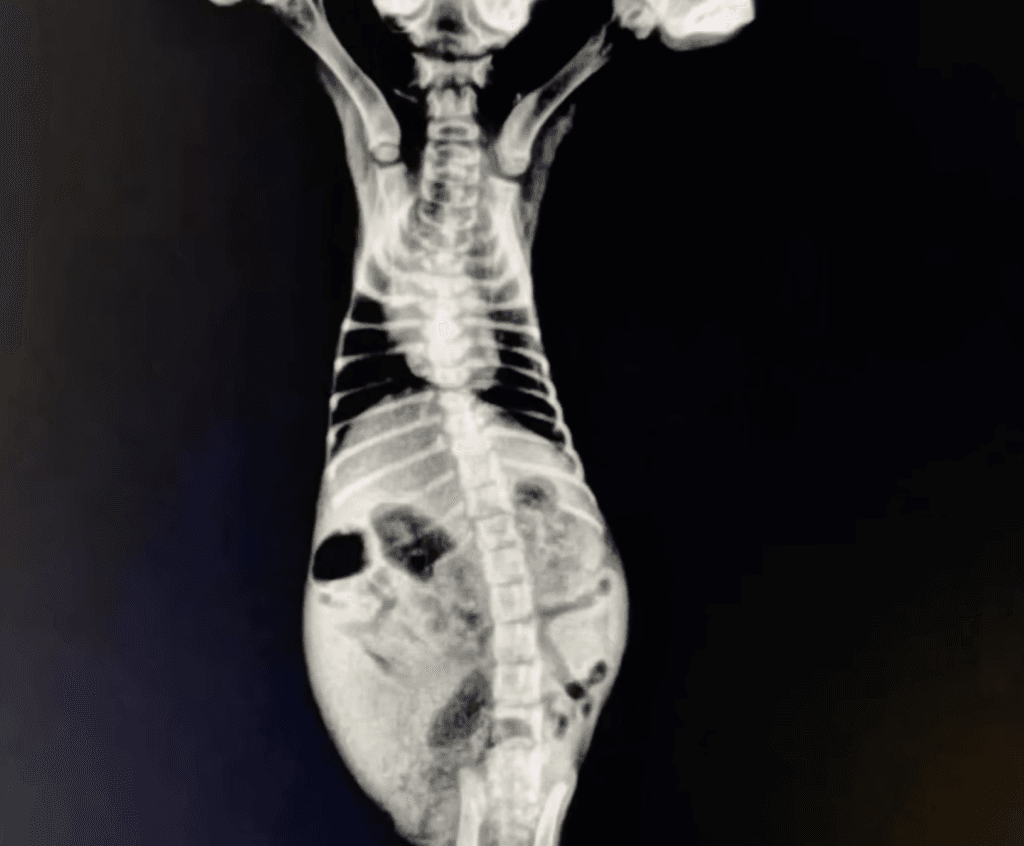

Gray soon noticed one of Jiu’s hind legs seemed weak while the other appeared swollen.

A vet visit suggested a possible congenital issue that might improve with growth, though nothing was certain.

Then came digestive troubles. Jiu lost her appetite and developed diarrhea, followed by vomiting.

Another visit to a 24-hour hospital ruled out major viruses, but the vet explained that she was simply very young and fragile.

During the exam, they discovered a deeper problem: a severe infected wound in her hind paw.

Soon after, a stool sample revealed intestinal parasites, confirming parasitic gastroenteritis.

Because Jiu weighed only 350 grams, most medications were too strong.

So the vet prescribed a gentler option and warned that she would need constant monitoring.